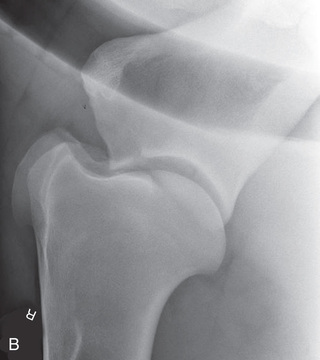

Shoulder Optional views | Mediolateral (ML) | Lateral (L) |

| Cranioproximal 45-degree medial–caudodistolateral oblique (CrPr45M-CaDiLO) | CrMCdLO | |

| Cranioproximal 45-degree lateral–caudodistomedial oblique (CrPr45L-CaDiMO) | CrLCdMO | |

To attain quality projections of the shoulder joint, the use of general anesthesia and placement of the patient in lateral recumbency are recommended. The standing position may be possible if the patient tolerates manipulation. The easiest and maybe only view of the shoulder that can be obtained is the mediolateral.